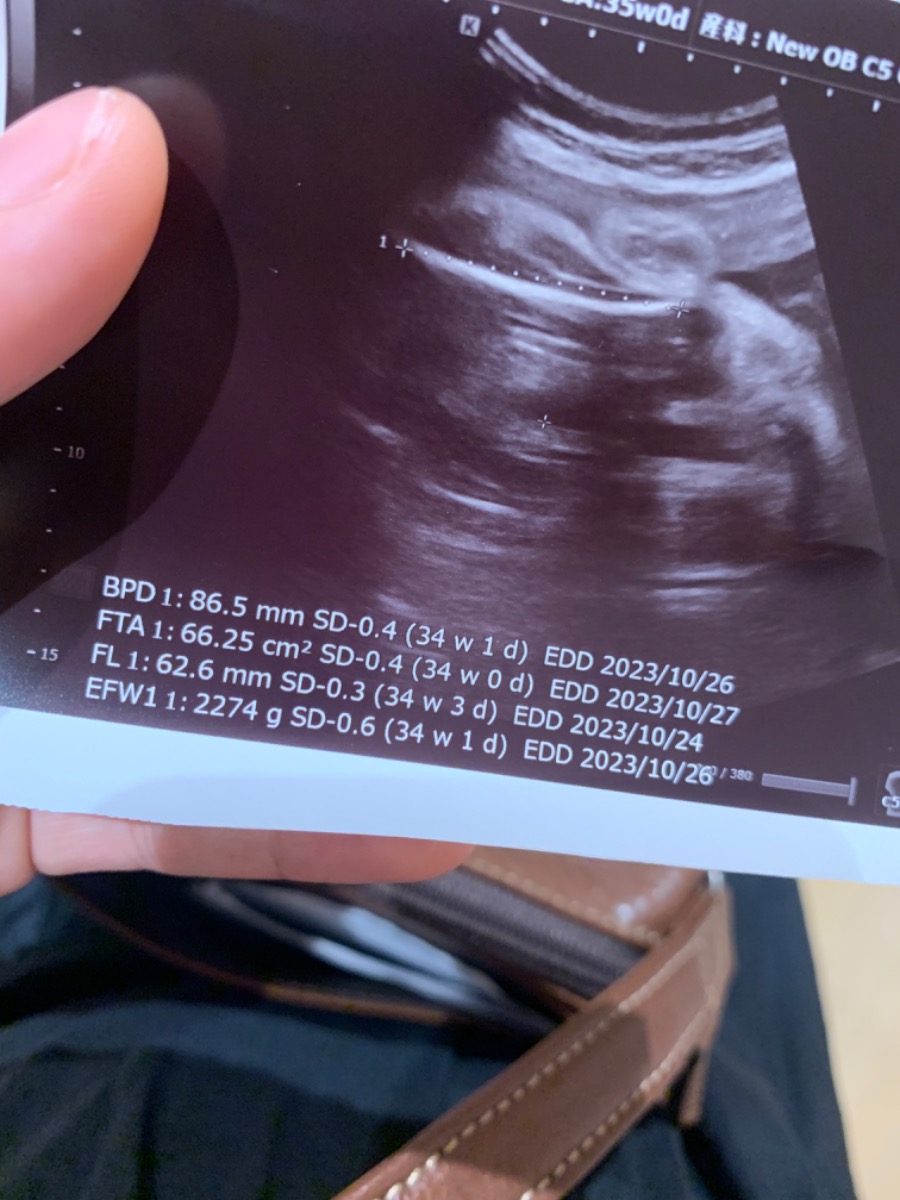

Admin ơi e hỏi ! Hnay e tuần 35 vừa đi khám xong thì theo chỉ số như ảnh thì có vấn đề gì k ạ ?

Trọng lượng tnay có bé quá k ạ